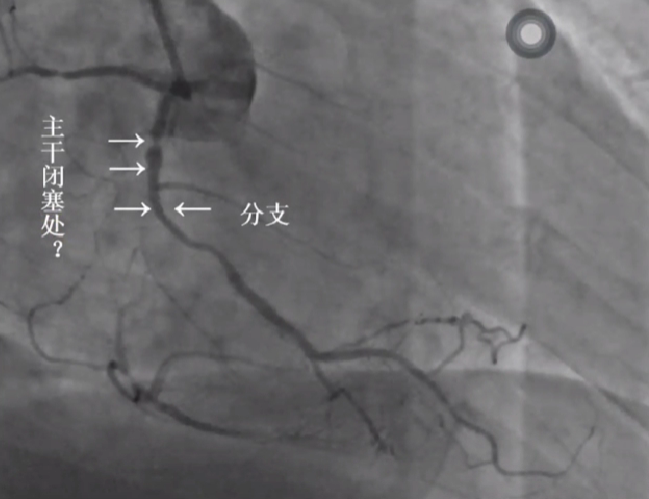

LAD闭塞处发出对角支 - 不易成功

右冠闭塞处不确切 - 不易成功